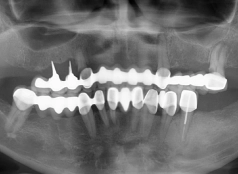

• Tình trạng răng trước đây:Mất nhiều răng hàm trên. Màu răng ố vàng, hình thể răng không đều

• Bác sĩ chỉ định:Cấy ghép Implant All On 6 hàm trên và Bọc răng sứ toàn hàm dưới

• Implant sử dụng:Trụ Implant Mis C1 Đức

• Răng sứ sử dụng:Răng toàn sứ Cercon HT Đức

• Cấy ghép Implant All On 6 hàm trên

• Bọc răng sứ toàn hàm dưới